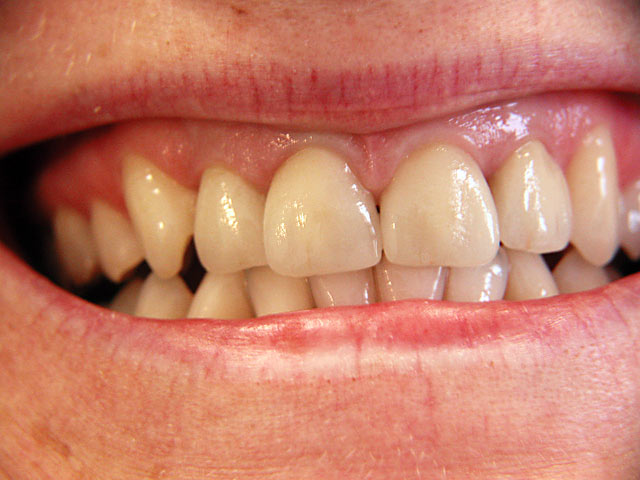

Frontzahn-Implantation: